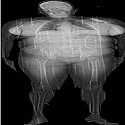

Volume 54 (May - Aug 2026)

This cover image JPEG | PDF